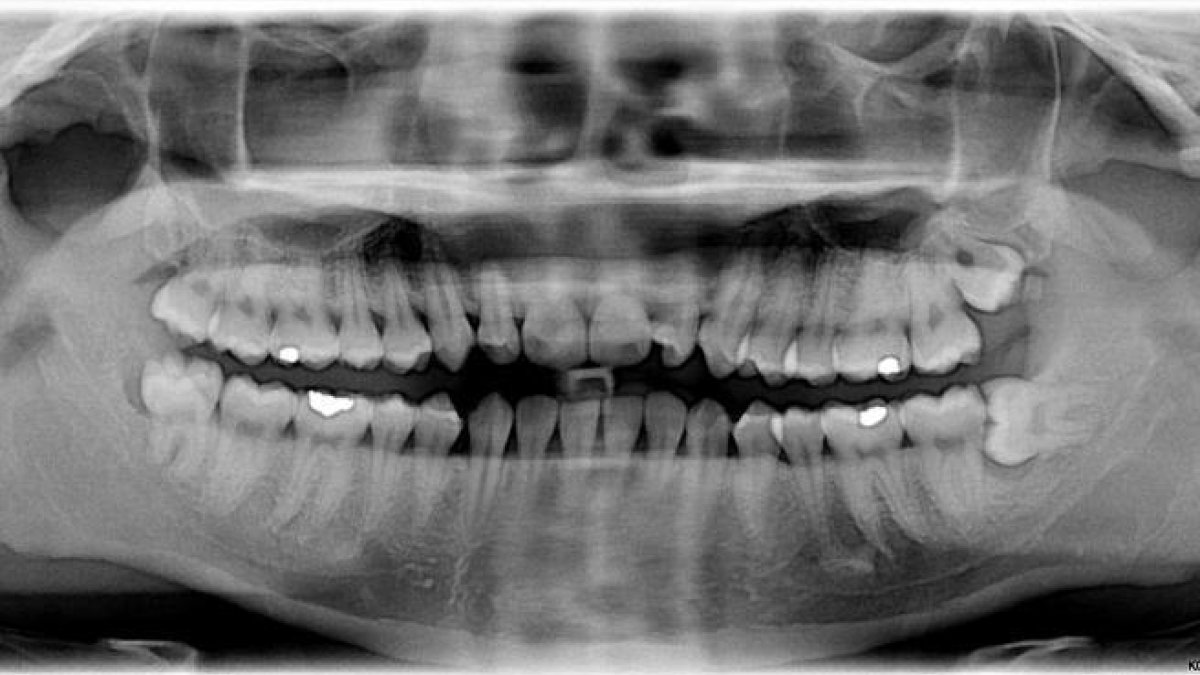

Las formas adultas de los dientes que usamos para triturar nuestra comida en una pasta generalmente emergen de nuestras encías en tres etapas: alrededor de los 6, de los 12 y de los 18 años de edad, aproximadamente.

Otros primates obtienen sus molares adultos antes. A pesar de todas nuestras similitudes en las etapas de crecimiento, el chimpancé (Pan troglodytes) obtiene sus molares a los 3, 6 y 12 años. El babuino amarillo (Papio cynocephalus) tiene sus últimos molares adultos a los siete años, y en el macaco rhesus (Macaca mulatta) todo está hecho para cuando tengan seis años.

Un factor importante que limita el momento en que pueden aparecer los dientes es el espacio. Si la mandíbula no es lo suficientemente grande para un conjunto dental de tamaño adulto, no tiene sentido apretarlos.

Los humanos no tienen exactamente mucho espacio en la boca, y las muelas del juicio impactadas son un problema importante para nuestra especie. Pero esto no explica por qué aparecen tan tarde en nuestras vidas, o por qué las mismas últimas parecen estar causando problemas cada vez más.